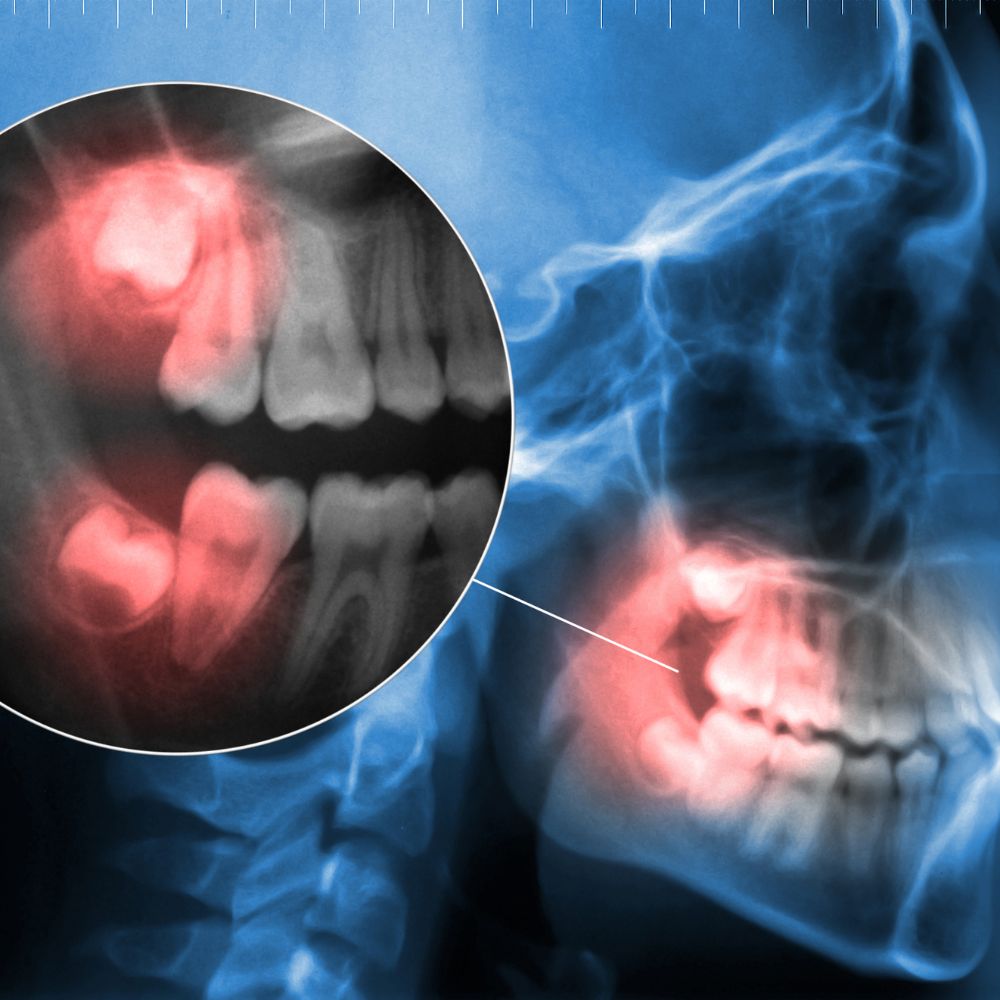

사랑니는 구강 내 맨 뒤쪽에 나오는 제3대구치로, 공간 부족, 비정상적 각도, 잇몸 염증, 인접치아 손상 등 다양한 문제를 유발할 수 있습니다.

특히 매복사랑니는 충치, 잇몸질환, 턱 통증, 얼굴 붓기 등 합병증 위험이 높아, 예방적 발치가 권장되는 경우가 많습니다.

- 매복사랑니는 잇몸과 뼈 일부를 제거해 치아 분할 발치

- 전문의에게 시술받기, 사전 CT·파노라마 촬영